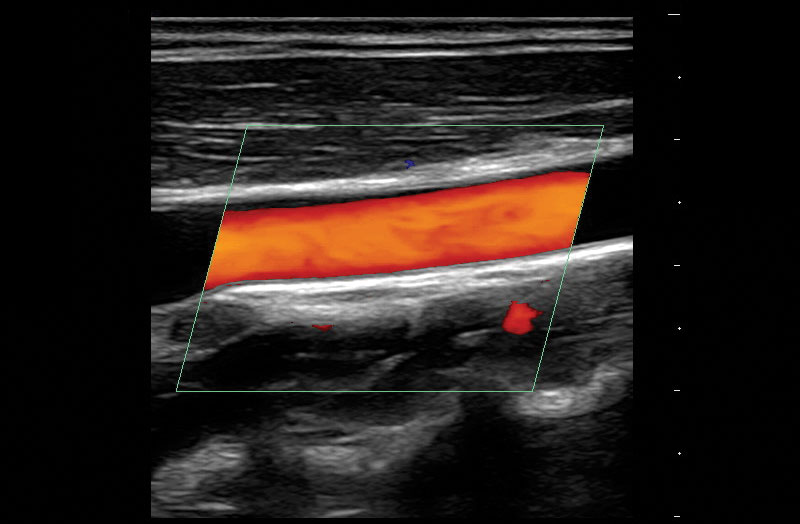

The Z.One PRO Ultrasound System Emerald Edition 2.0 is a powerful and portable advanced point-of-care imaging platform. Powered by software-based ZONE Sonography® Technology+ (ZST+), the Z.One PRO System provides optimal B-mode and Doppler imaging for patients, regardless of body habitus, helping ensure a reliable diagnosis. With a full family of transducers (from 2 – 20 MHz) and a wide range of applications, the Z.One PRO System is the imaging answer to your difficult clinical cases.

Advanced needle visualization technology allows increased needle visibility even during steep-angled procedures, while maintaining superior image quality. Improved confirmation of needle location in tissue minimizes harm to surrounding tissue.